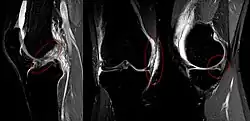

La tríada de O'Donoghue, también llamada tríada desgraciada o tríada infeliz, es una lesión compleja de rodilla en la que existen tres lesiones diferentes de forma simultánea: rotura del ligamento cruzado anterior, rotura del ligamento lateral interno y rotura del menisco interno. Se provoca como consecuencia de traumatismos sobre la rodilla, predominando en varones jóvenes y con mucha frecuencia en relación con la práctica deportiva, sobre todo del fútbol. El diagnóstico se basa en la sintomatología y se confirma mediante la realización de radiografía, resonancia magnética nuclear y artroscopia. El tratamiento es siempre quirúrgico seguido de un periodo de rehabilitación y fisioterapia.[1]